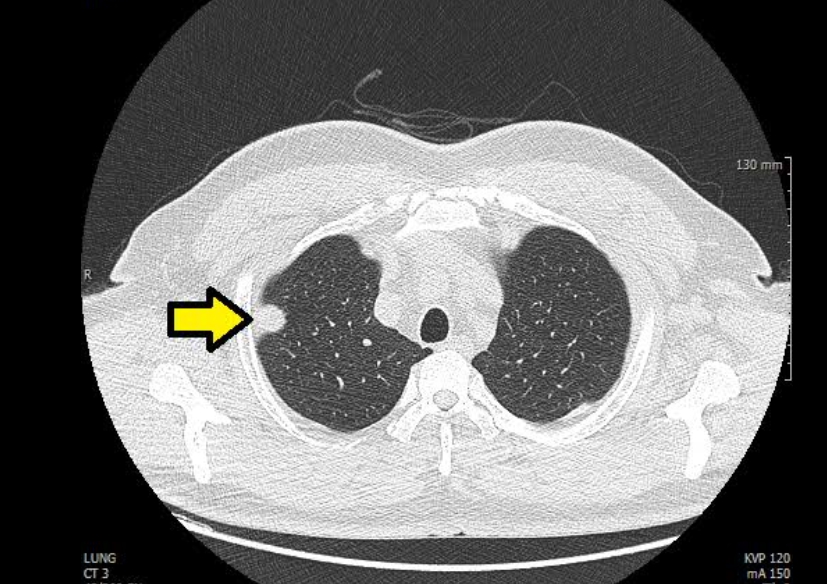

폐 편평세포암은 폐암의 한 유형으로, 주로 흡연과 관련이 있습니다. 기침이 3주 이상 지속되거나 피 섞인 가래, 숨이 차는 증상이 있으면 검사를 받아야 합니다. 흡연자는 비흡연자보다 편평세포암 발생 위험이 몇 배나 높습니다. 금연은 가장 강력한 예방책이며, 폐 건강을 지키는 가장 직접적인 방법입니다.

진단은 흉부 X선, CT, 기관지 내시경, 조직검사로 이뤄집니다. 치료는 수술, 방사선, 항암치료, 면역치료가 병합됩니다. 최근에는 맞춤형 치료제가 도입되어 생존율이 향상되고 있습니다.